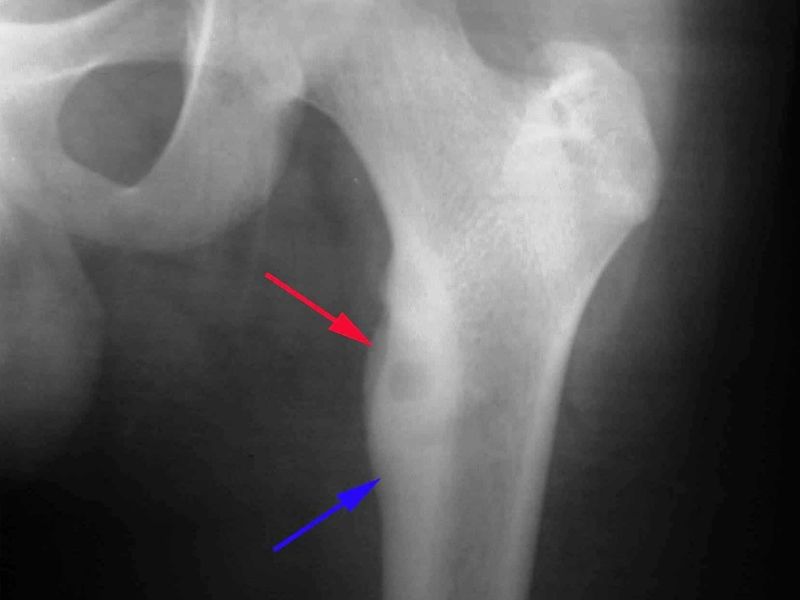

- Chụp X-quang: Là phương pháp chẩn đoán hình ảnh đầu tiên và phổ biến nhất để phát hiện bất thường trong cấu trúc xương, giúp xác định vị trí khối u, hình dạng, mật độ và mức độ ảnh hưởng đến mô xương xung quanh. Hình ảnh X-quang có thể cho thấy các dấu hiệu như vùng mất xương (tiêu xương) hoặc tạo xương bất thường.

- U xương ác tính thấp: chiếm 1% đến 2% trong số tất cả các u xương ác tính, chủ yếu xuất hiện ở các xương dài của người trưởng thành trẻ tuổi.

- Sarcoma xương ở xương mác: 1% đến 6% bệnh ung thư xương, phát triển chậm, xuất phát từ bề mặt ngoài của phần xương.